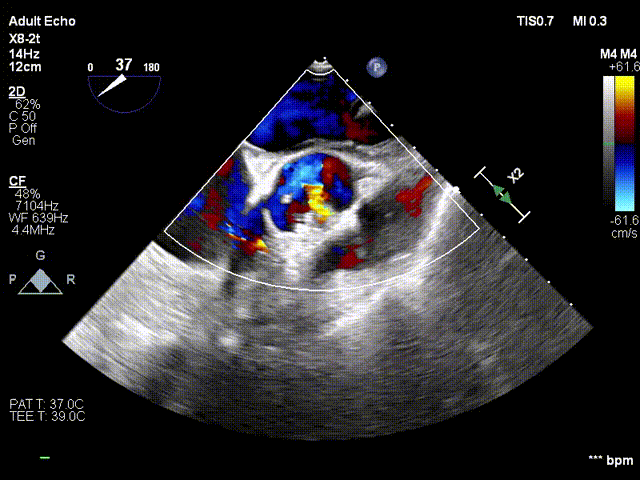

术前、术后超声对比

术前

术后

术后评价

术后超声显示瓣口未见明显反流,无瓣周漏,主动脉瓣前向血流加速Vmax=1.65m/s,有效开口面积1.61cm²,PGmean=4mmHg。术后监测,心率心电正常,无传导阻滞。患者生命体征稳定。本次手术植入瓣膜定位准确,操作简便,症状即刻改善,手术圆满成功。